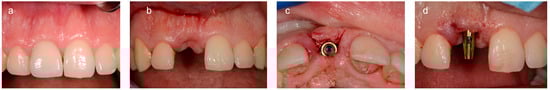

2.2. Analogic Work-Flow

2.3. Digital Work-Flow

- Dental arch with the cemented provisional crown,

- Provisional crown connected with a digital analogue,

- Dental arch with a scan body screwed onto the implant.